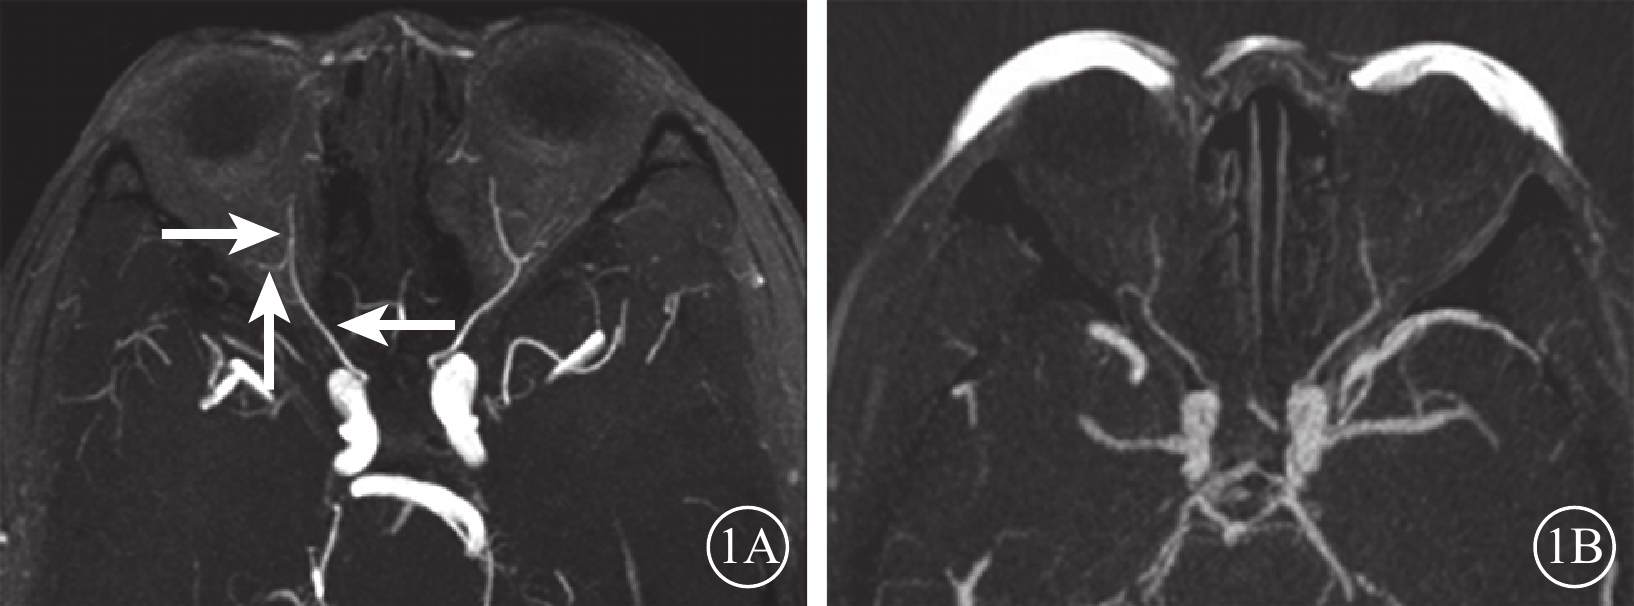

對照組44只眼中,眼動脈MRA 0級41只眼(93.2%);Ⅰ級3只眼(6.8%),其中鼻背動脈和淚腺動脈顯影淺淡2只眼,鼻背動脈顯影中斷1眼。行眼動脈CTA檢查的10只眼均為0級(圖1)。

圖1

對照組受檢者MRA、CTA像。1A. MRA;1B. CTA。雙側眼動脈走行自然,起始部及主干均未見明顯病變及異常中斷,遠端主要分支內側鼻背動脈及外側淚腺動脈走行自然,顯影良好,未見明顯病變及異常中斷(白箭)

圖1

對照組受檢者MRA、CTA像。1A. MRA;1B. CTA。雙側眼動脈走行自然,起始部及主干均未見明顯病變及異常中斷,遠端主要分支內側鼻背動脈及外側淚腺動脈走行自然,顯影良好,未見明顯病變及異常中斷(白箭)

對照組44只眼中,眼動脈MRA 0級41只眼(93.2%);Ⅰ級3只眼(6.8%),其中鼻背動脈和淚腺動脈顯影淺淡2只眼,鼻背動脈顯影中斷1眼。行眼動脈CTA檢查的10只眼均為0級(圖1)。

圖1

對照組受檢者MRA、CTA像。1A. MRA;1B. CTA。雙側眼動脈走行自然,起始部及主干均未見明顯病變及異常中斷,遠端主要分支內側鼻背動脈及外側淚腺動脈走行自然,顯影良好,未見明顯病變及異常中斷(白箭)

圖1

對照組受檢者MRA、CTA像。1A. MRA;1B. CTA。雙側眼動脈走行自然,起始部及主干均未見明顯病變及異常中斷,遠端主要分支內側鼻背動脈及外側淚腺動脈走行自然,顯影良好,未見明顯病變及異常中斷(白箭)